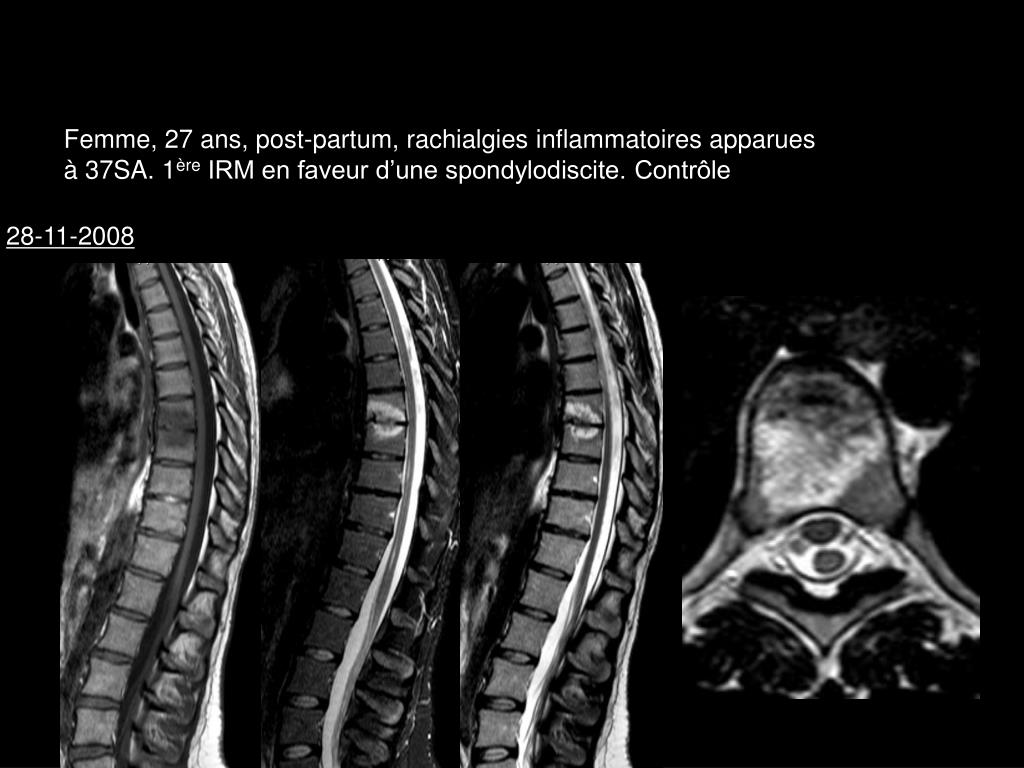

10. Femme, 27 ans, post-partum, rachialgies inflammatoires apparues à 37SA. 1ère IRM en faveur d’une spondylodiscite. Contrôle 28-11-2008